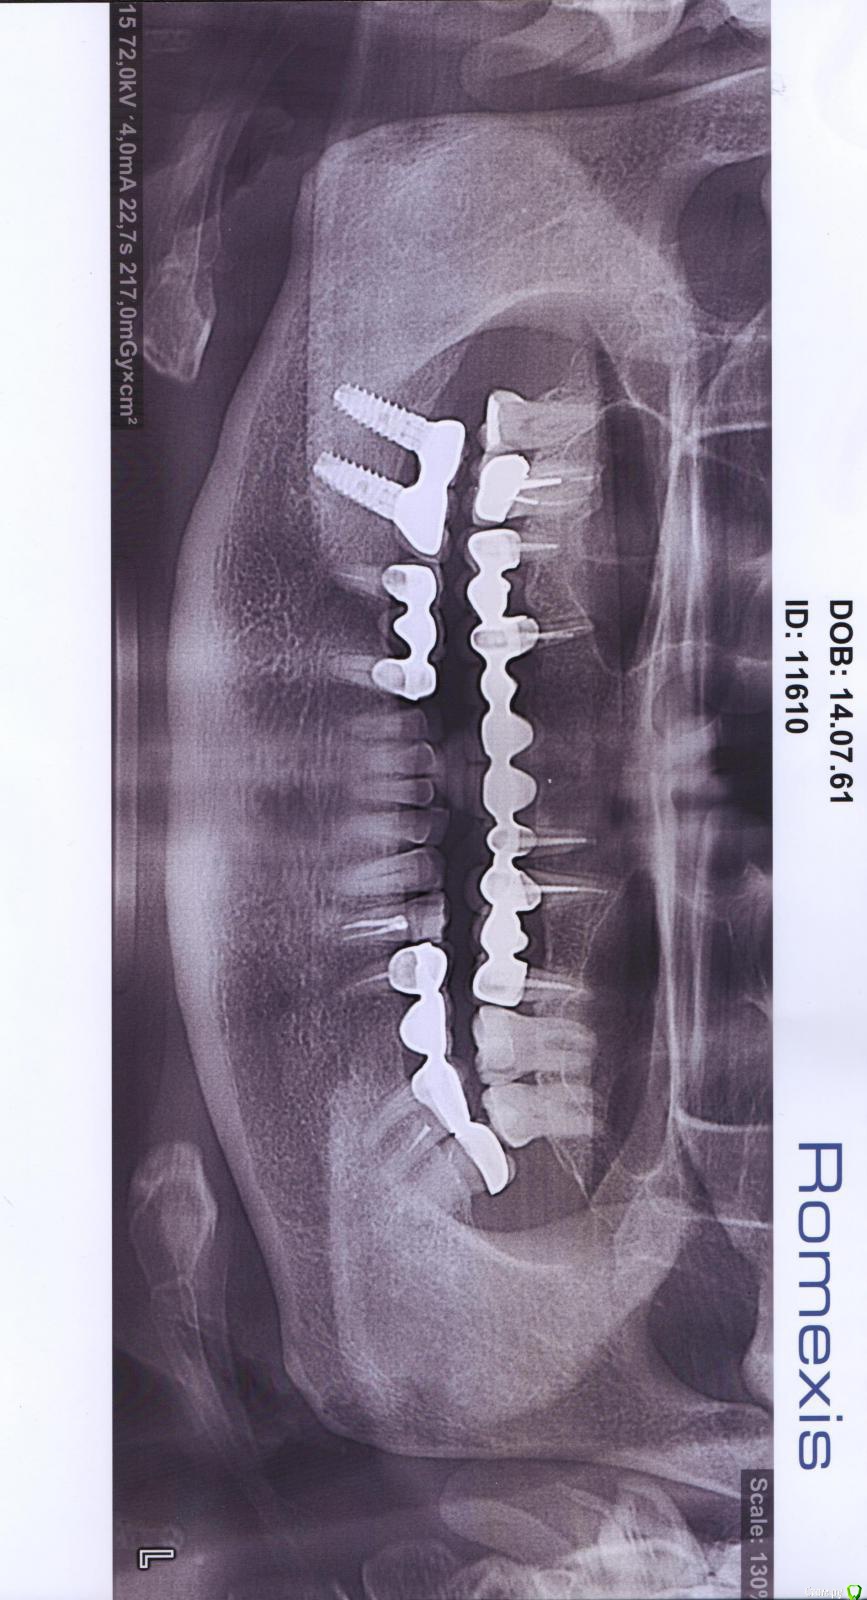

Pomaikai Опубликовано 4 февраля, 2015 Поделиться Опубликовано 4 февраля, 2015 Здравствуйте! Подскажите пожалуйста. Ситуация такова. Моей маме (54 года) требуется протезирование 10 зубов на верхней челюсти. После посещения стоматолога пришла очень расстроенная, говорит, что доктор отговаривает от имплантов, говорит лучше съемный поставить. Мотивирует такой совет тем, что кость (как я понимаю дуга верхней челюсти) очень плохая, тонкая и будут серьезные проблемы при имплантации, ибо одним имплантом не обойтись, нужно несколько, а для челюсти это будет очень высокая нагрузка. Вот сейчас решаем. Не хотелось бы съемный... но и рисковать не хочется. Не знаем что делать. Идти к другому врачу или соглашаться на такой вариант. Не знаю имеет ли значение, но мама болеет саркоидозом. Ортопантомограмму прилагаю. Ссылка на комментарий

АнтонТЛТ Опубликовано 4 февраля, 2015 Поделиться Опубликовано 4 февраля, 2015 Внизу стоят же без проблем? Сходите на консультацию к другому врачу. Если недостаток костной ткани, то понадобится костная пластика и пластика десны Ссылка на комментарий

Pomaikai Опубликовано 4 февраля, 2015 Автор Поделиться Опубликовано 4 февраля, 2015 Внизу стоят же без проблем?Сходите на консультацию к другому врачу. Если недостаток костной ткани, то понадобится костная пластика и пластика десны Спасибо огромное! Подскажите пожалуйста на сколько это удорожит процедуру (костная пластинка и пластика десны). Что касается нижней челюсти, то доктор пояснил это тем, что там большой массив костной ткани в отличии о верхней, где ее недостаток. Ссылка на комментарий